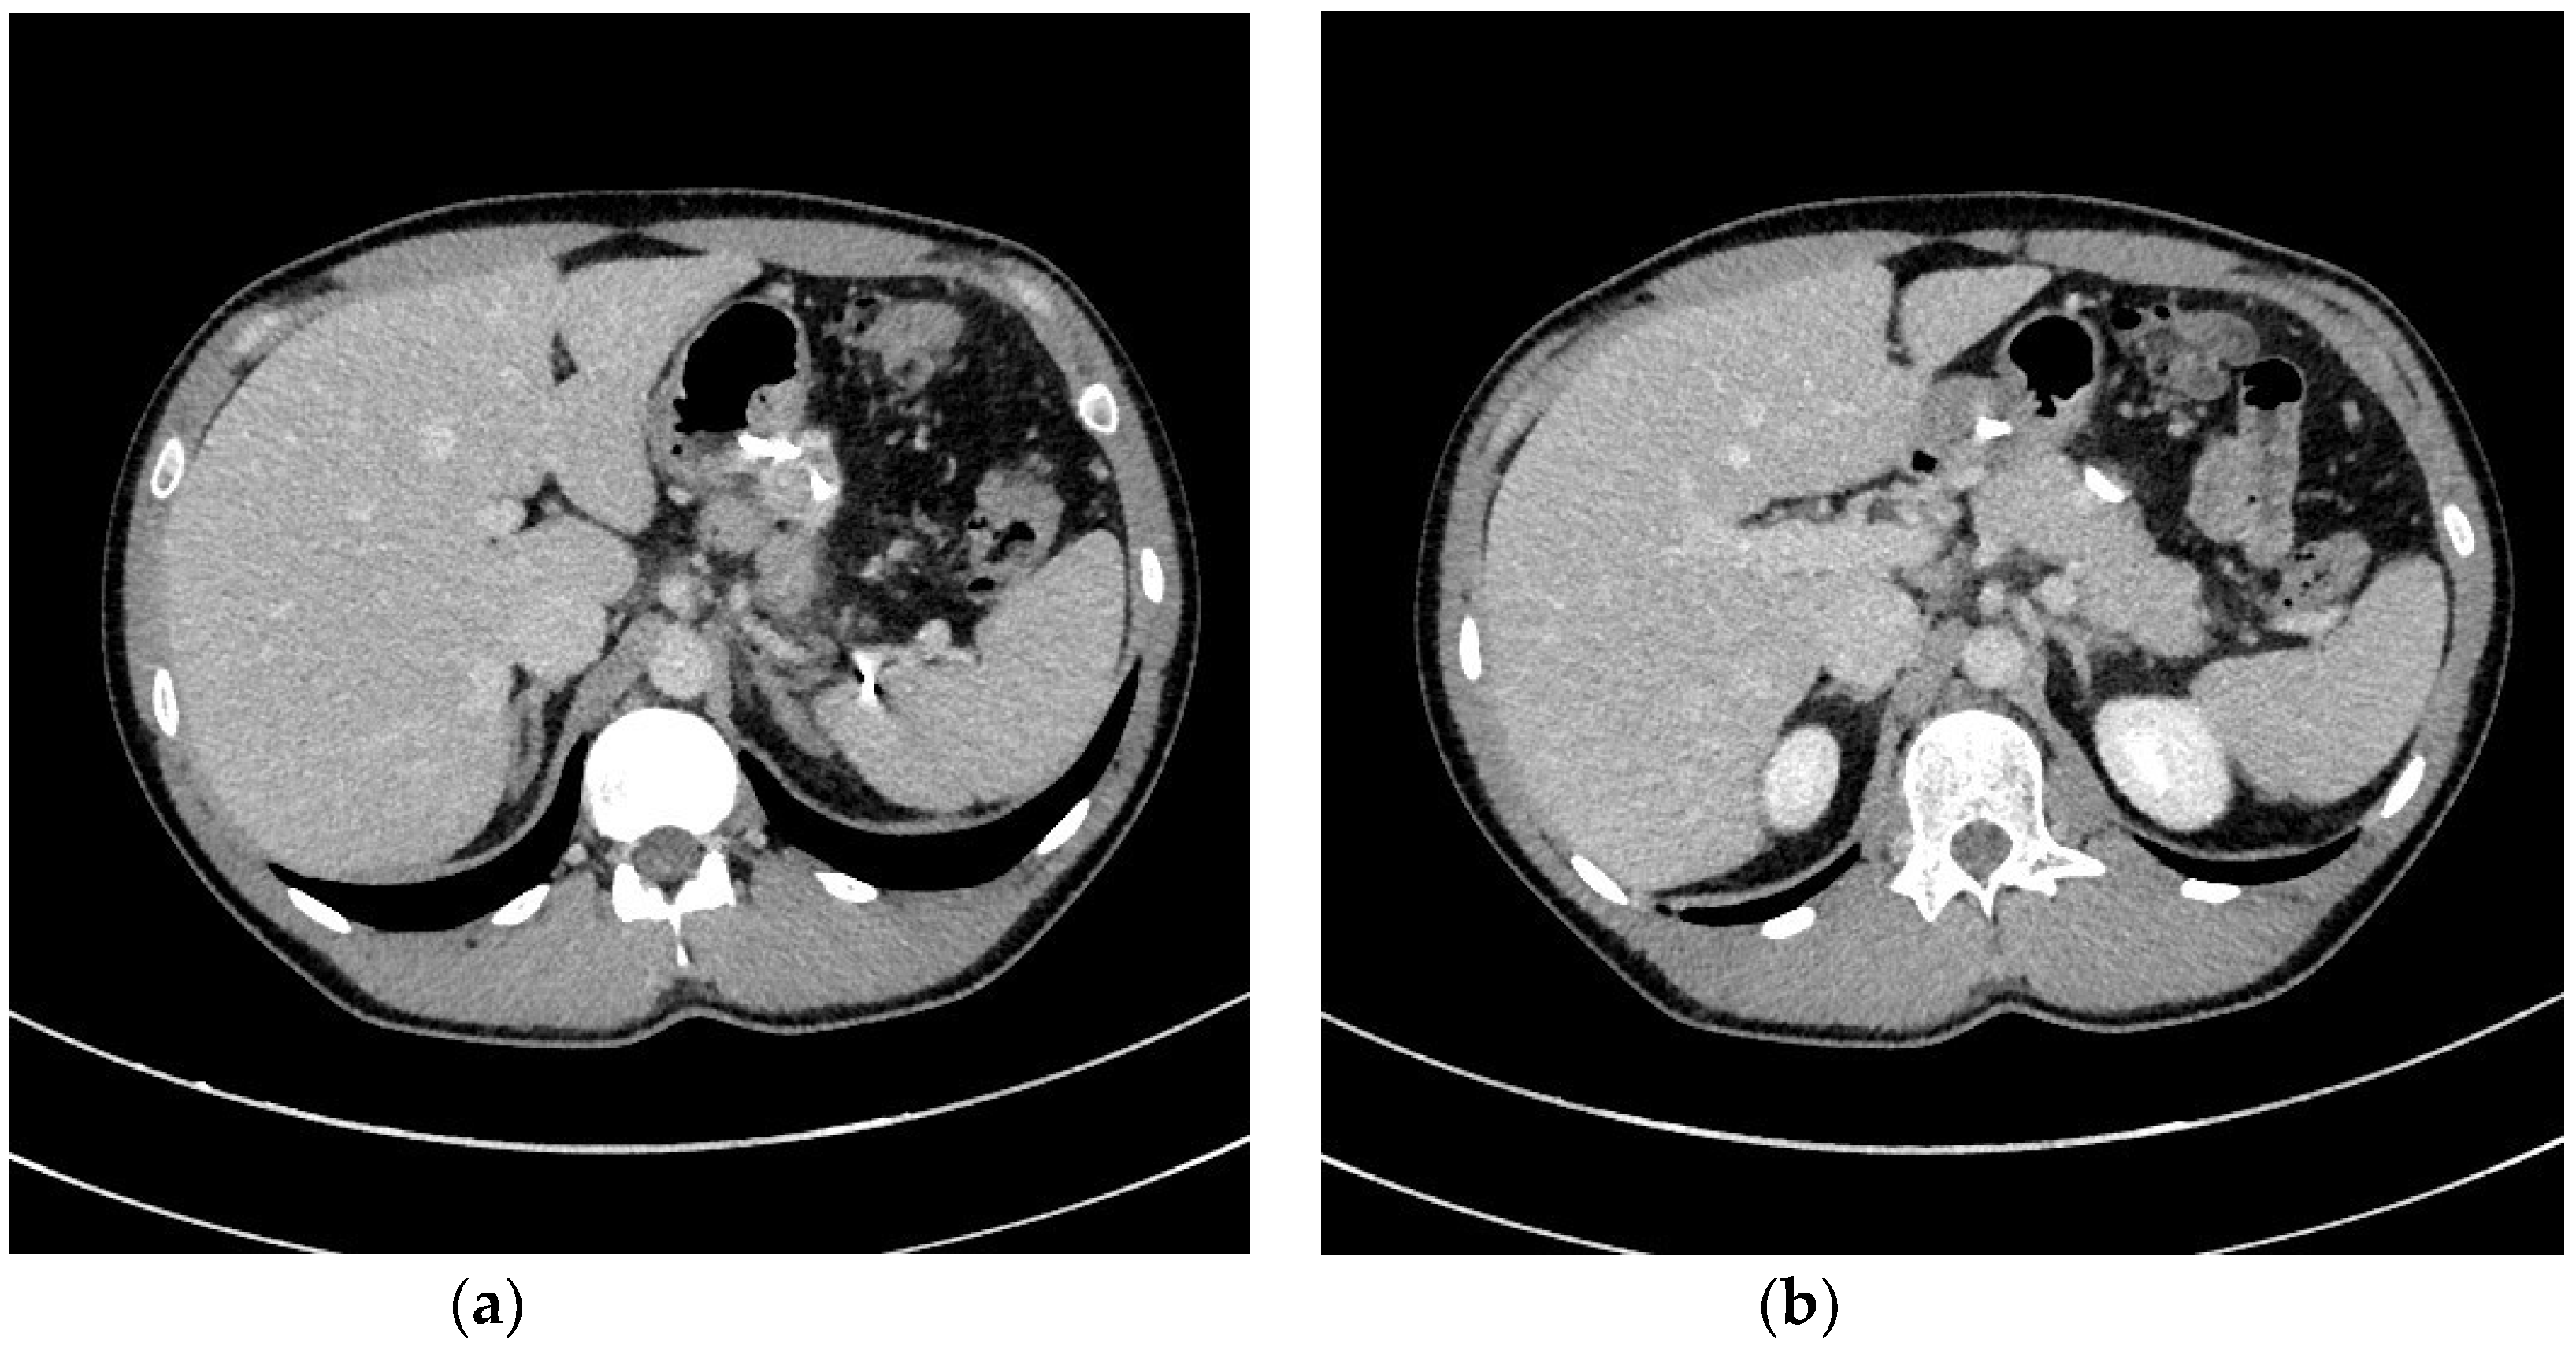

| Endoscopic necrosectomy under fluoroscopic guidance (endoscopic debridement) | Procedure that enable to remove necrotic tissues from necrotic cavity through transmural fistula under fluoroscopy with use of various types of endoscopic tools. Indication for endoscopic debridement is WOPN containing poorly-liquefied necrotic tissues. |

| Direct endoscopic necrosectomy | Procedure accomplished via insertion of endoscope through the transmural fistula into the lumen of WOPN and direct removal of necrotic tissues under endoscopic view with use of different types of endoscopic tools. Direct endoscopic necrosectomy is usually technically easier to proceed during transmural drainage with use of SEMSs. Indications for direct endoscopic necrosectomy are extensive WOPN containing poorly-liquefied necrotic tissues without clinical improvement despite active transmural drainage. |